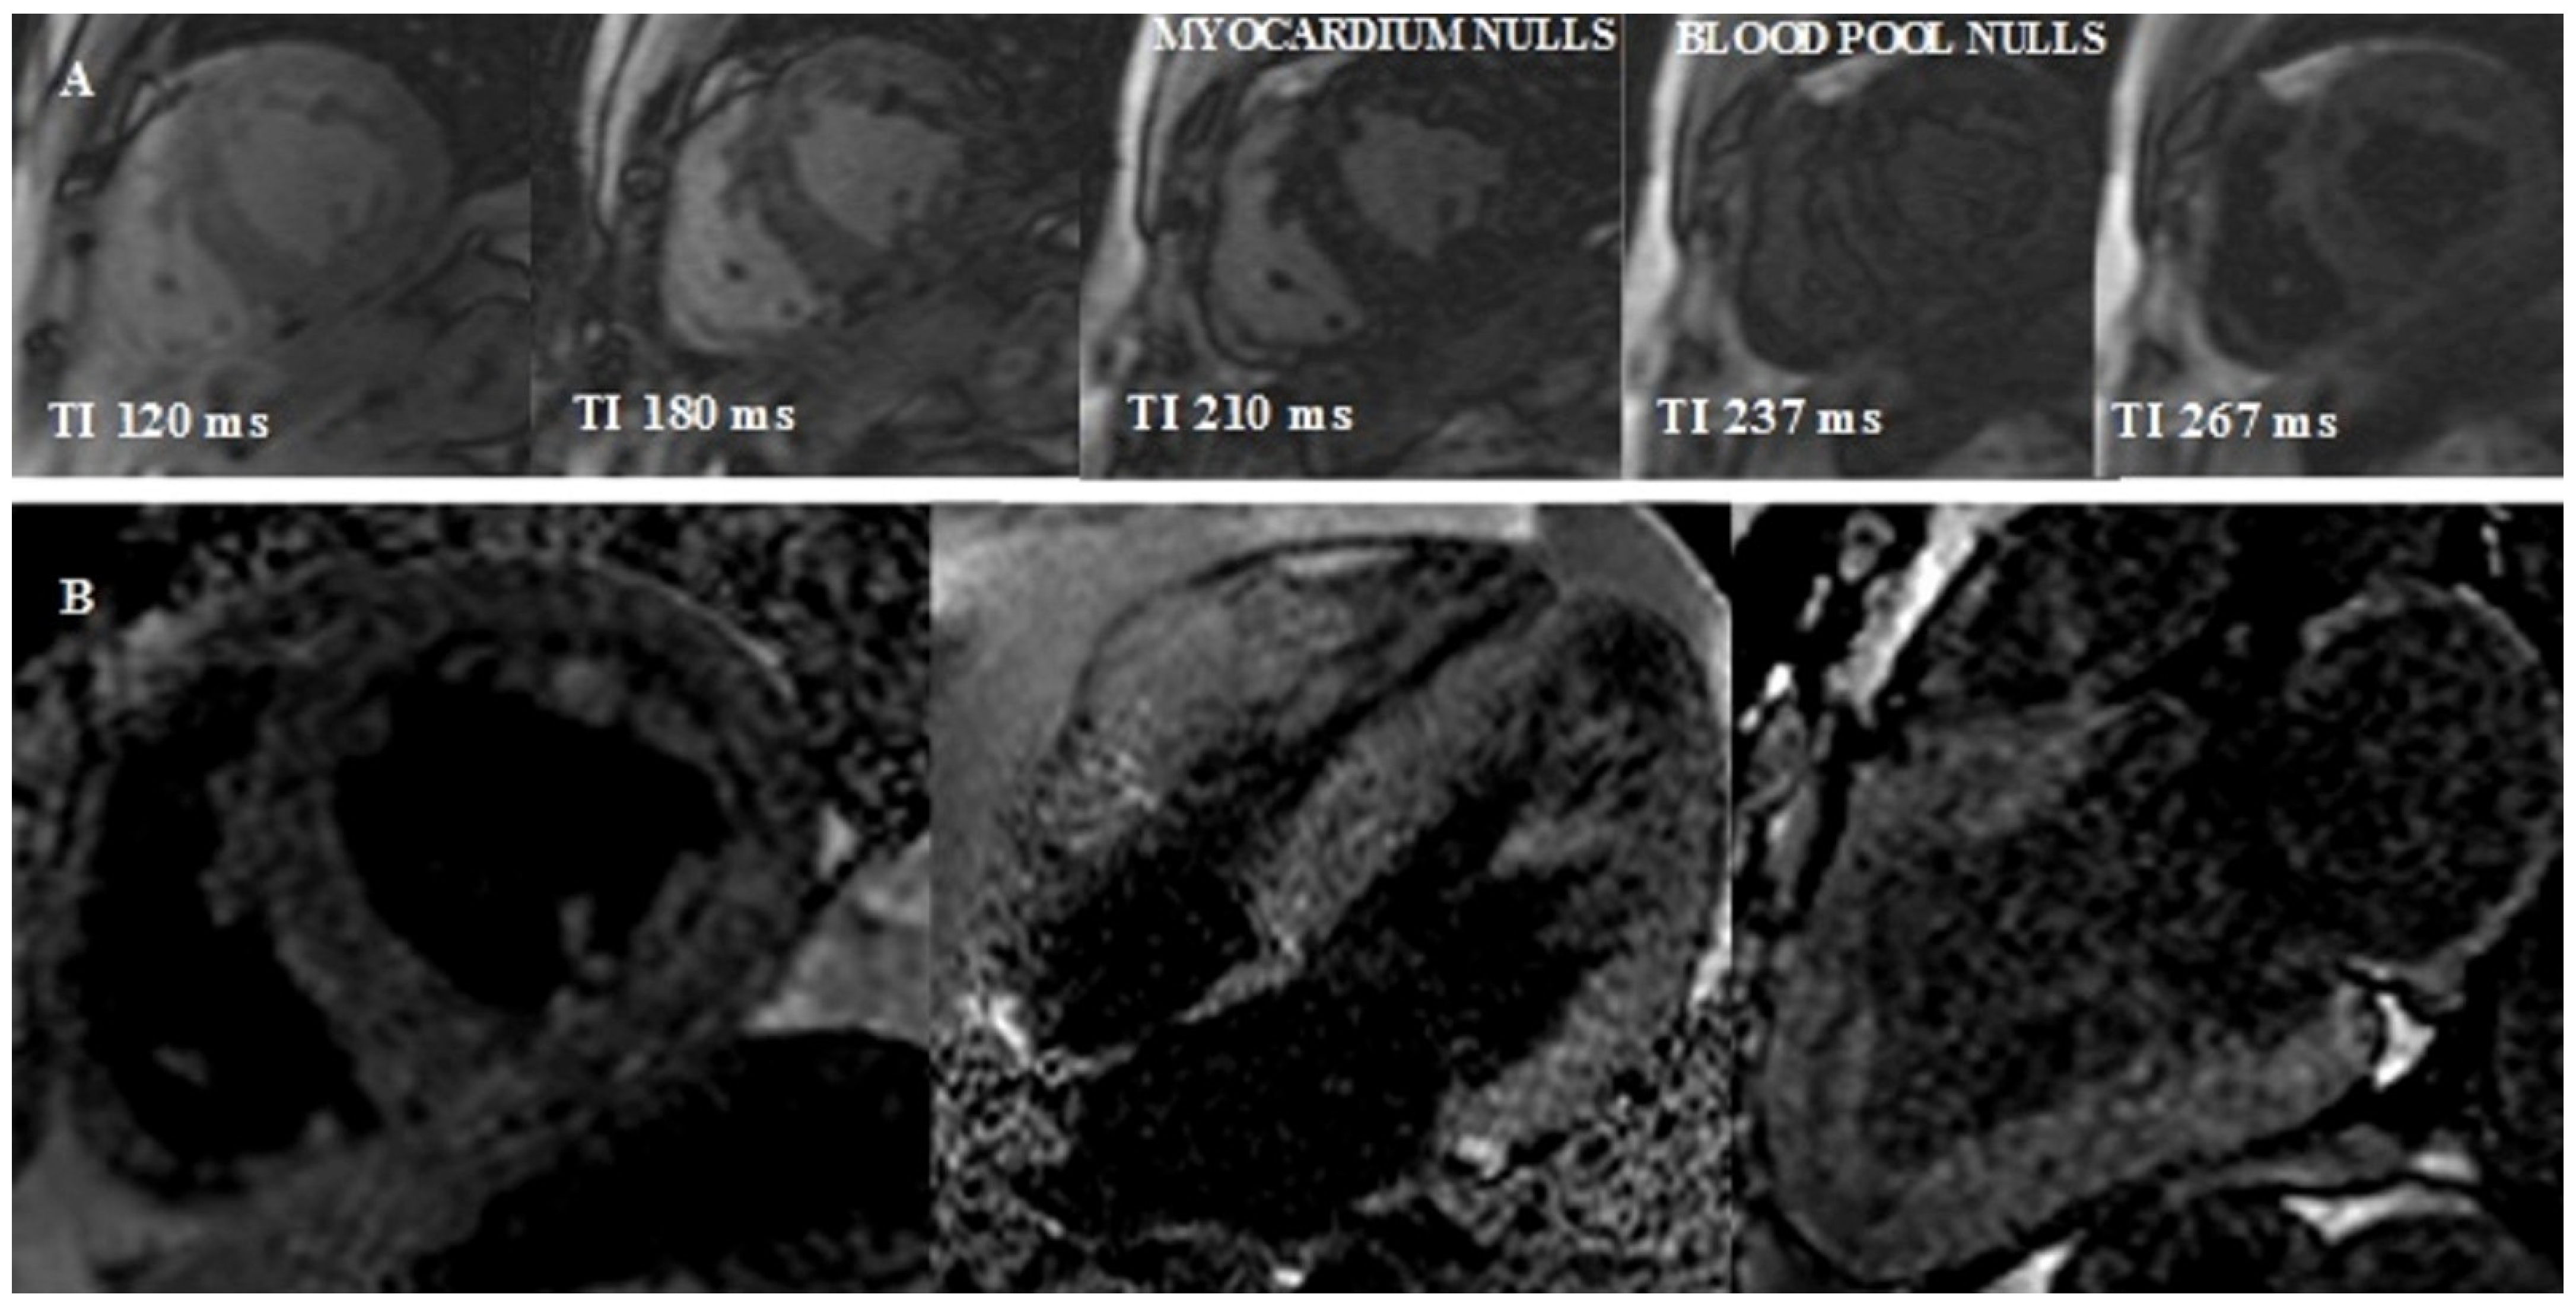

- Look-Locker TI scout. The optimal inversion time to null the normal myocardial signal is determined using a Look–Locker TI scout sequence acquired in the short-axis at the mid-ventricular level ∼5 min after the administration of contrast. The pattern of nulling is classified as normal if the blood pool is nulled before the myocardium. In CA the pattern is reversed, blood pool nulling being coincident with or after myocardial nulling (Figure 4).